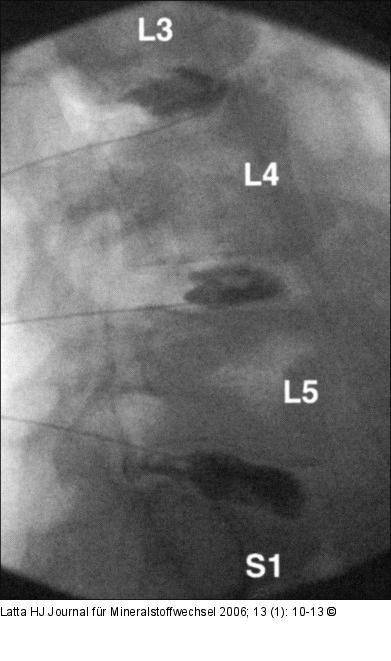

Abbildung 6a-b: Lumbale Provokationsdiskographie Lumbale Provokationsdiskographie mit periduralem KM-Austritt bei L5/S1. |

Lumbale Provokationsdiskographie mit periduralem KM-Austritt bei L5/S1. |